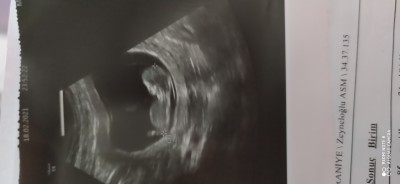

Nub teroisine göre cinsiyet bilen varsa yorumlayabilir mi

image

Nub bilmiyorum ama kız gibi sanki narin duruyor maşallah Rabbim sağlıkla kucağına almayı nasip etsin

Kiz gibi sanki canım. Minik çıkıntı var ya ayak kisminda o çok yukariya bakiyorsa erkek nuba göre bilmiyorum ama doğruluğunu:D

Nubu bilmiyorum icimden kiz demek geldi :)